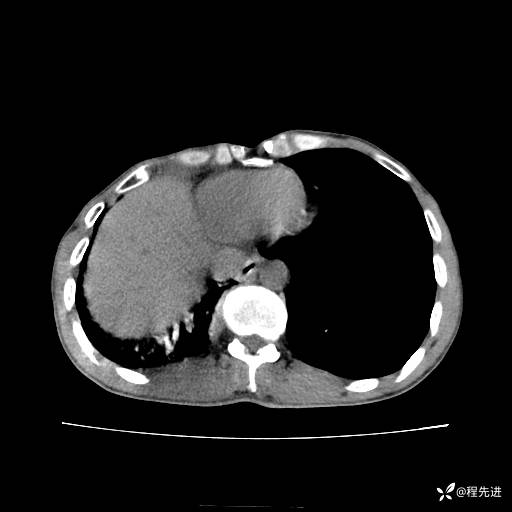

患者性别:男

患者年龄:49岁

主诉:咳嗽、胸痛1周

简要病史:1周前受凉感冒后开始出现咳嗽症状,阵发性连声咳,痰多,黄白痰,不易咳出,伴胸痛、气紧、胸闷,右侧为主,活动用力、呼吸时胸痛明显,曾在当地诊所贴敷膏药仍疼痛

体格检查:T:36.3 ℃ P:80 次/分 R:20 次/分 BP:120/88 mmHg,指脉氧饱和度97%,意识清晰,呼吸平稳,右侧第二、三肋骨压痛,可见膏药贴敷,皮肤无异常,双肺呼吸音粗,未闻及干湿性啰音。心率80次/分,节律整齐,无杂音。腹平软,全腹无压痛无反跳痛

临床诊断:社区获得性肺炎

CT平扫: